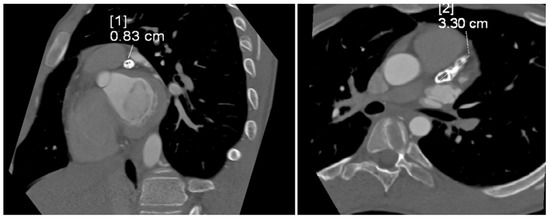

The tubular, highly calcified structure, without any features of contrasted lumen, measuring 8.3 × 15 × 33 mm, was confirmed by CT angiogram of the coronary vessels (Figure 3). Relating the dimension obtained from imaging studies to the Z-score classification of coronary artery abnormalities, we obtained a Z-score of +11.2, which, together with an absolute dimension ≥ 8 mm according to the guidelines, corresponded to a giant aneurysm.

Figure 3.

Computed tomography angiogram showing tubular, highly calcified, left coronary aneurysm (8.3 × 15 × 33 mm) without any features of contrasted lumen. Diameter [1]—8.3 mm; diameter [2]—33 mm.